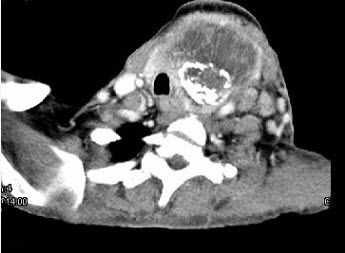

女,64岁,发现双甲状腺肿大一月余,CT如图所示,最可能诊断为()。

A、结节性甲状腺肿

B、甲状腺腺瘤

C、甲状腺癌并淋巴结转移

D、甲状腺转移癌

E、甲状腺结核

C